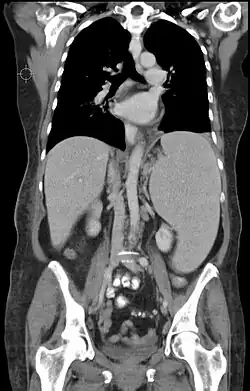

![]() | |

| Medula óssea de uma pessoa com leucemia linfoblástica aguda de percursores B. Coloração de Wright | |